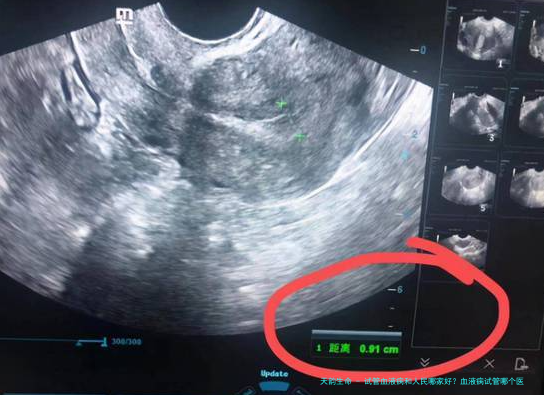

血液病试管哪个医生好?

大体上血液疾病医院做试管的话,在试管周期的时候归属于流水性操作,医生同是进行排号,而在试管前检查以后就可以挂武泽、官洁、拜如霞等专家号,需要注意的是必须挂到医生的号将来才会看,另外专业人士只是定方案,而进行周期将来就需要选择其他医生,所以不用担心,每一位医生都是比较的,要有决心信念。